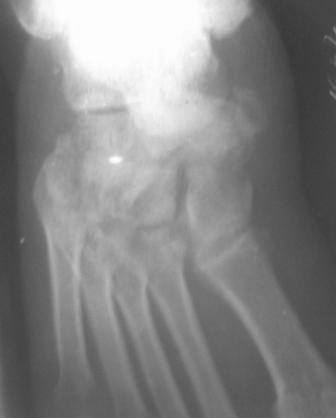

Уважаемый Абдурашид, с большой долей вероятности можно говорить о том, что в результате ДТП пациент плучил вывих в суставе Шопара с переломом одной из костей, скорее всего, действительно ладьевидной. Подтвердить это можно, попытавшись сделать более качественные ргр плюс снимки косым лучом для идентификации передних отделов таранной кости и таранно-ладьевидного сустава. Как я понимаю, выполнить КТ для данного пациента маловероятно. Тогда попробуйте воспользоваться таким старым, но в ряде случаев эффективным методом, как сравнительные Ргр здоровой конечности. Если Вы подтвердите д-з вывиха, а скорее да, по сохраняющемуся подвывиху, да иначе и сложно себе представить, как произошло такое смещение фрагмента, и, учитывая срок с момента травмы, Вам придётся выполнить артродез таранно-ладьевидного и, скорее всего, пяточно-кубовидного сочленений. С уважением, Волна

По данному случаю, оказалось 3 месяца назад было произведена Р-графия в райбольнице, но больной предпочел лечится у табиба. Присылаю первичные снимки.

Да, наш с Вами диагноз, Абдурашид, подтвердился. Я бы предпочёл артродез, фиксация- в самом простом варианте-винтами 3,5 или 4,5 . Отломок послужит аутотрансплантатом. Плюс внешняя иммобилизация. С уважением, Волна